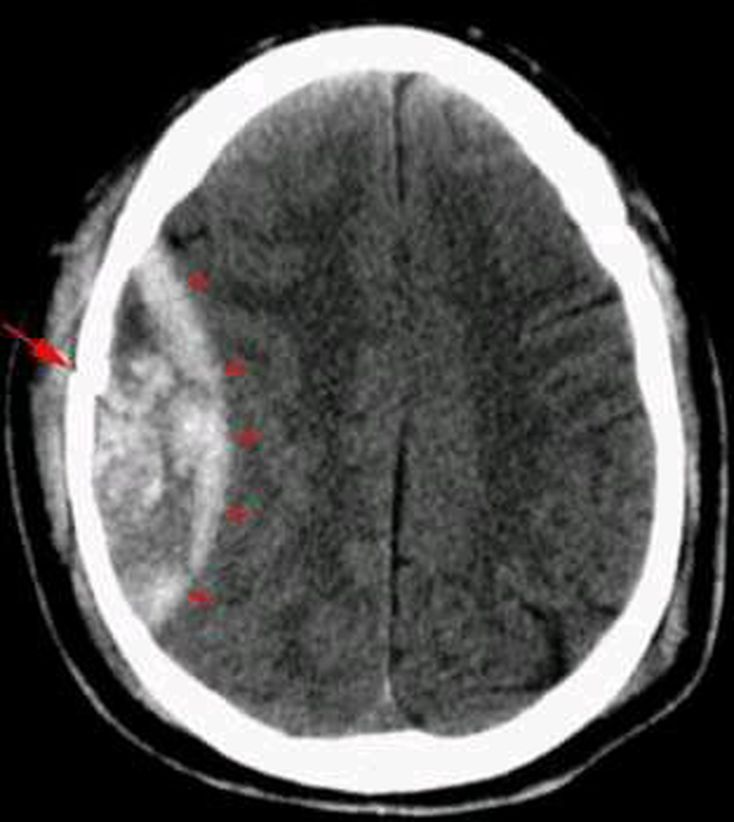

What is your diagnosis?

Epidural hematoma(lens shape) with skull fracture

EDH with skull fracture